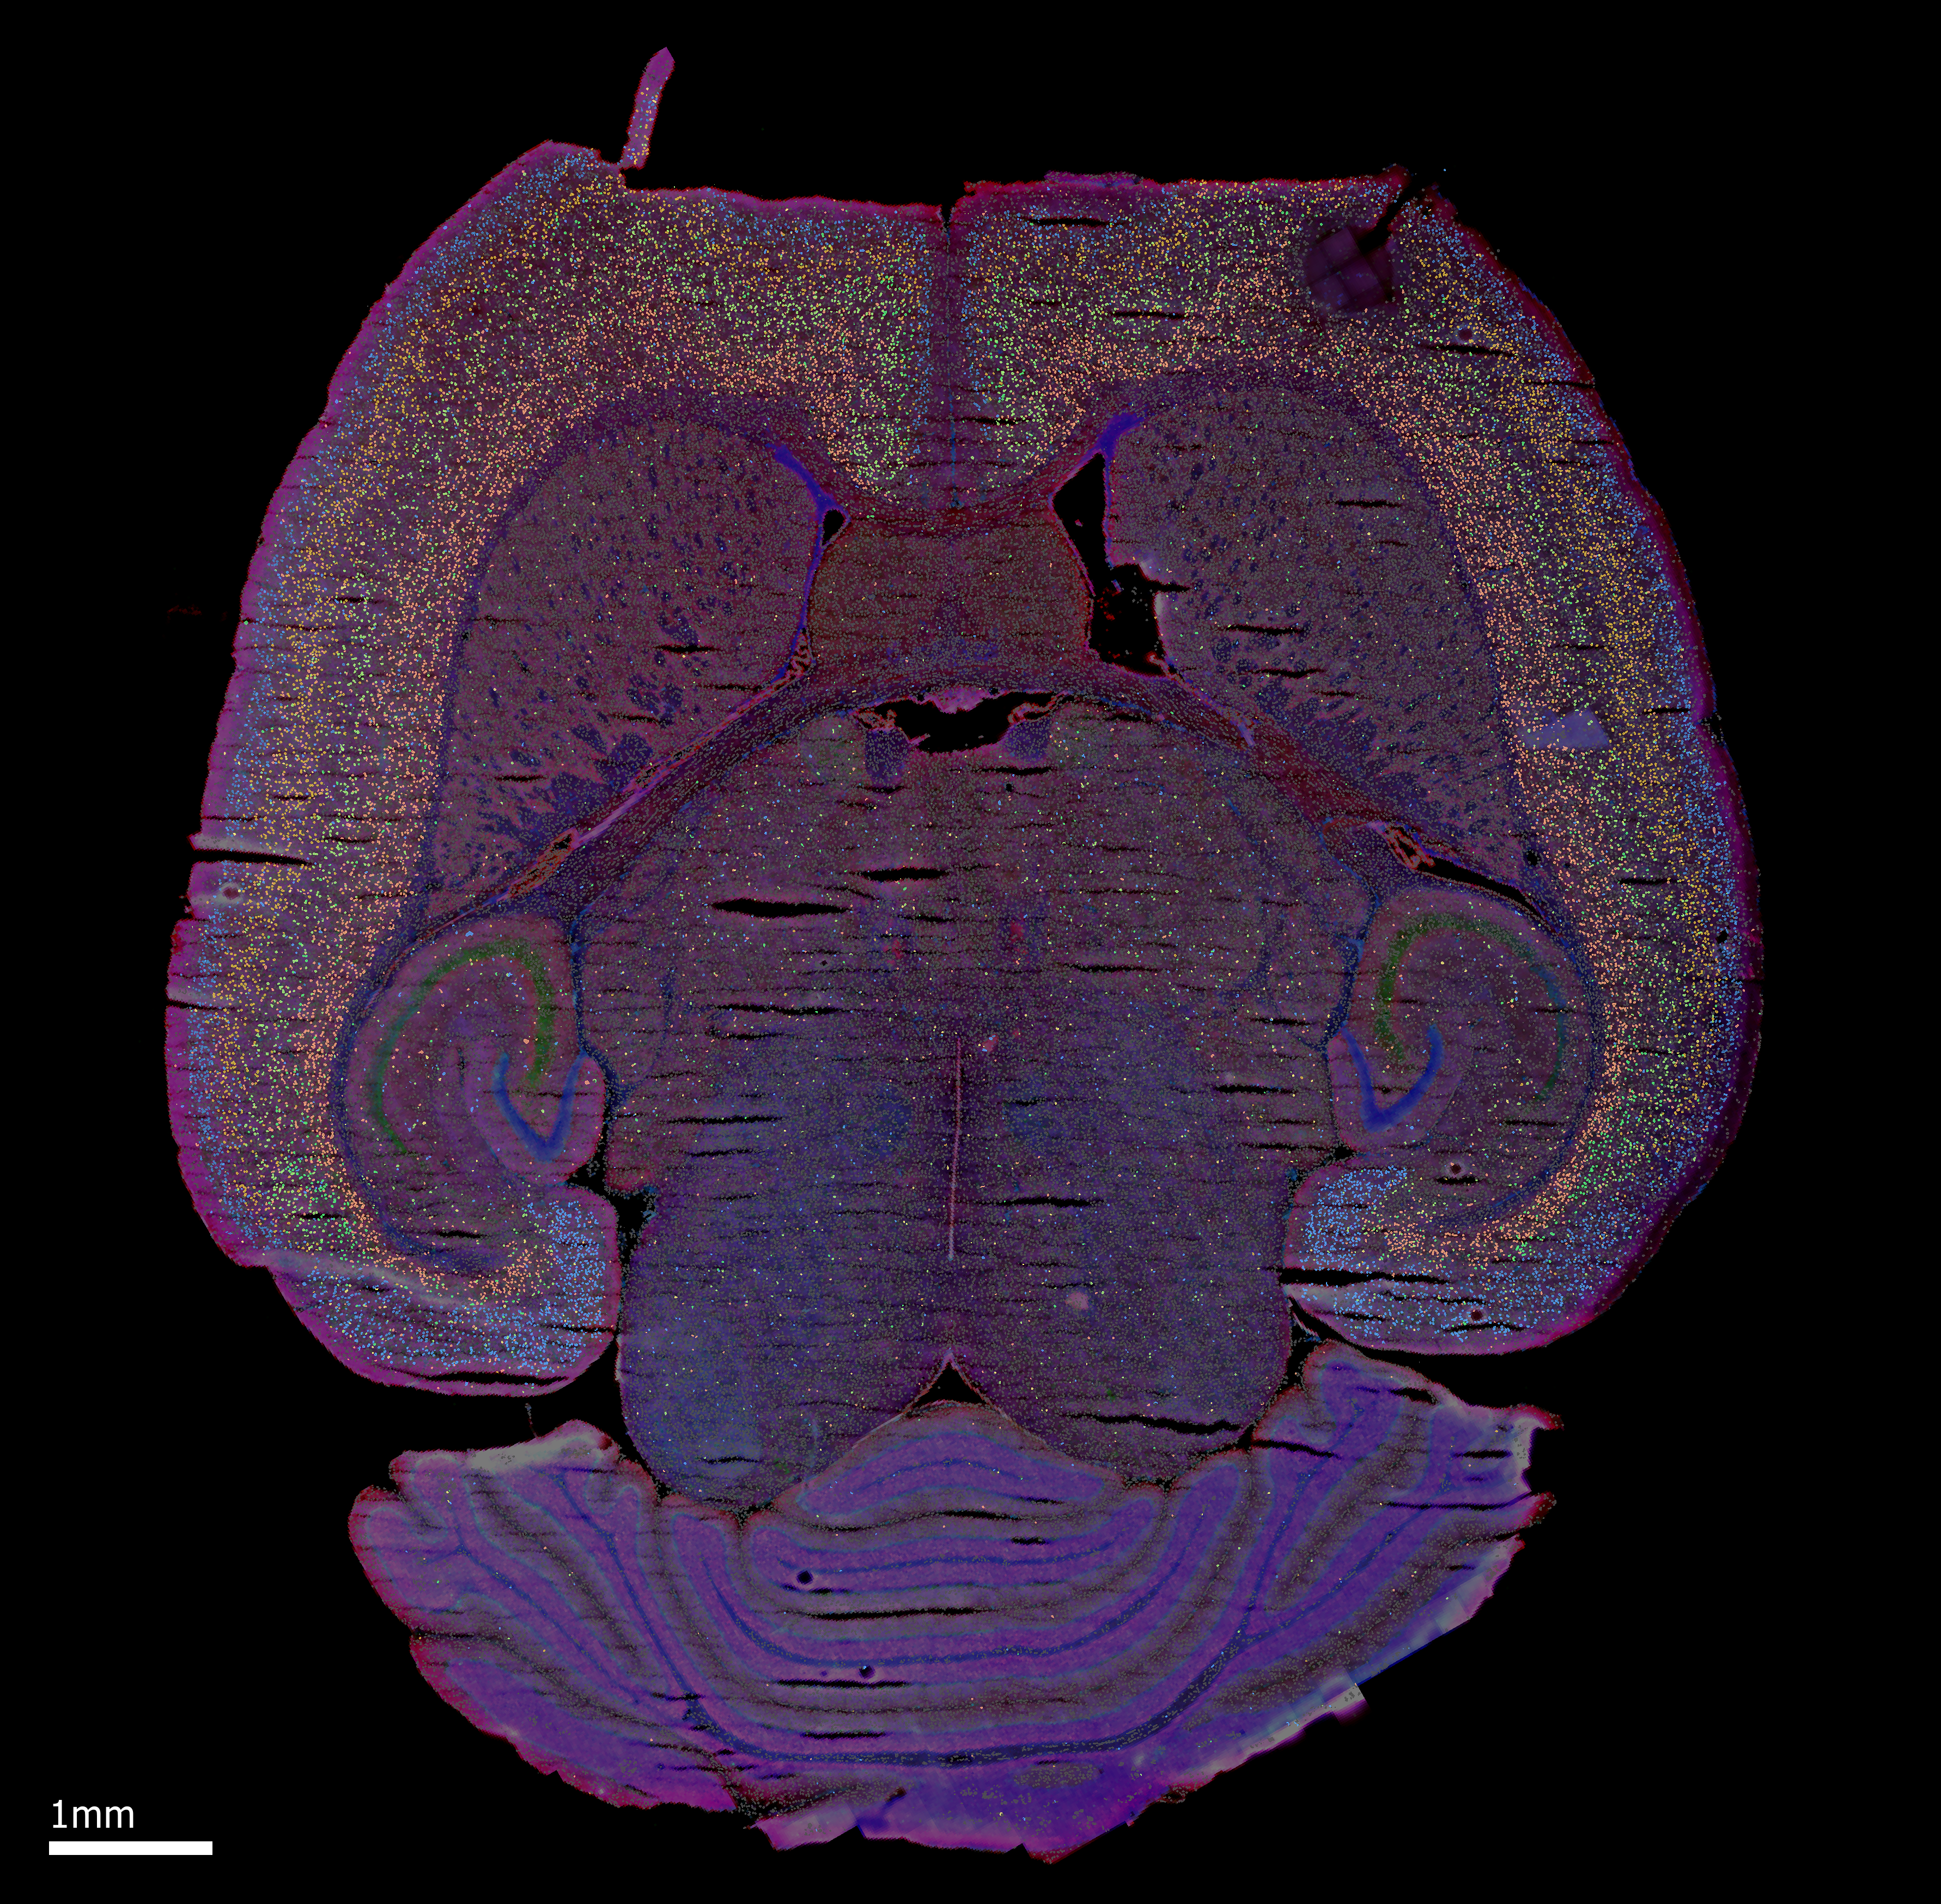

The mechanisms by which the auditory cortices develop unique sound processing capabilities remain unknown. Recent research conducted in our lab has indicated notable variations in the maturation trajectory of the auditory cortices. To gain insights into the molecular pathways responsible for these differences, we investigate changes in gene expression between the auditory cortices using spatial transcriptomics.